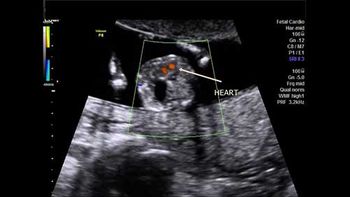

This 18-week fetus has a vascular anomaly. Can you identify it?